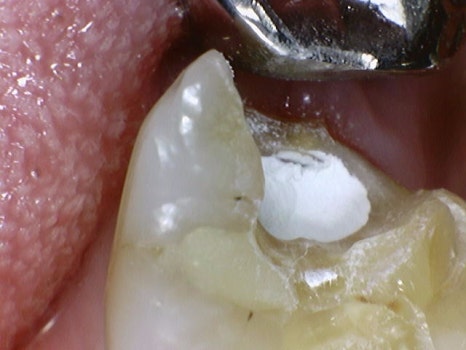

신경의 노출 , MTA 재료의 이용

신경의 입구는 뾰족하게 튀어나와있기 때문에

충치를 제거하다 보면 신경 입구가 노출되는 경우가 생깁니다.

이럴 경우 MTA 라는 재료를 사용하면 신경치료없이 신경을 살리는 시도를 해볼 수 있습니다

단, 항상 사용할 수 없고 증상에 맞게 사용하더라도 낮은 확률로 신경치료가 필요한 경우가 있습니다.

왼쪽 사진과 같이 빨갛게 보이는 부분이 신경이고

신경이 아직 살아있는 경우에 한 해 MTA라는 재료를 사용할 수 있습니다

MTA란 생체친화적 재료로 치유력, 재생력, 항균능력이 높은 재료로 알려져 있습니다.

치료 과정에서는 지혈 -> 재료 적용 -> 재료경화순으로 굳는데 걸리는 시간이 추가적으로 소요되기 때문에

예정에 없던 진료시간이 길어질 수밖에 없습니다.